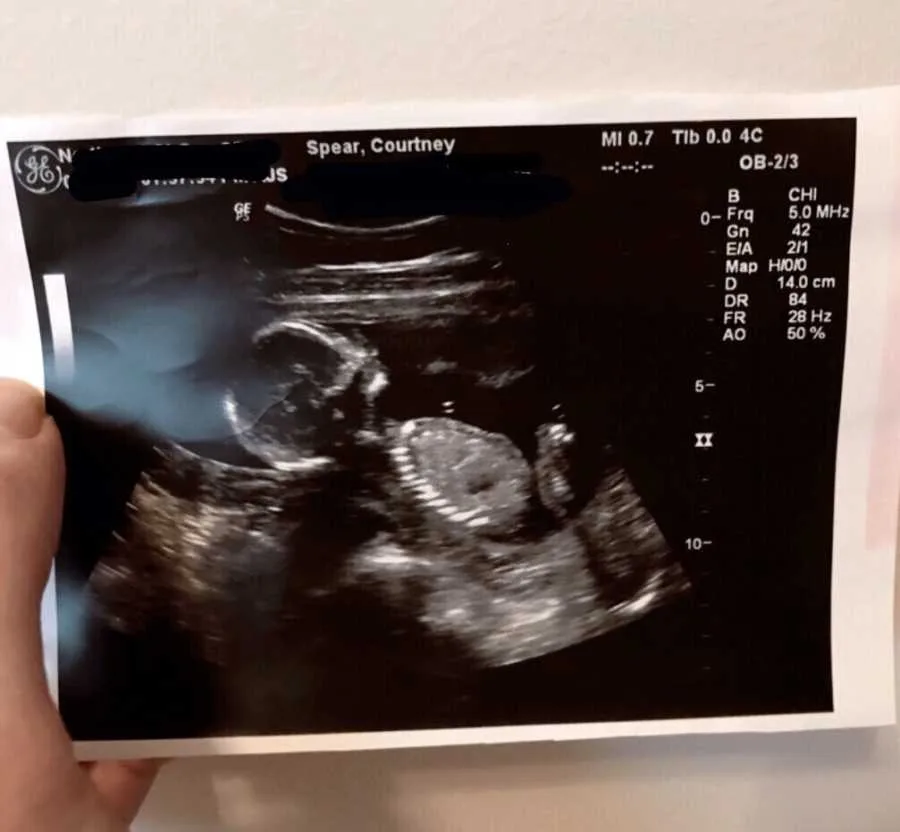

However, one day, she woke up feeling different. This feeling led her to take a pregnancy test, which showed two pink lines. She was expecting! Realising that she would embark on a journey so many pray for, despite her health conditions, felt like a miracle.

Although most doctors urged the couple to abort the baby as the chances of survival of the mother and child were rare, another doctor gave her hope. As months passed, the complication seemed to grow from constant bleeding to preterm labour. She was able to go through it all, and in the next few months, she gently held her angel in her arms. Her first son’s cry was everything to her!